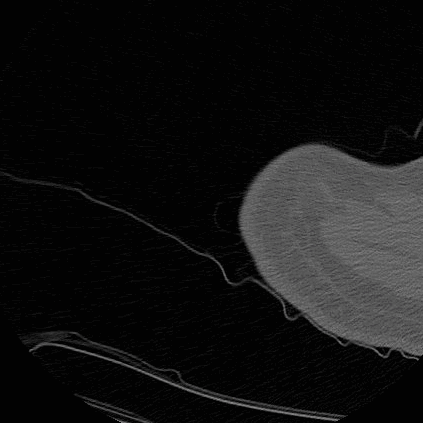

CT Humerus Contrast- Bone window (axial)

CT Humerus Contrast- Bone window (coronal)

CT Humerus Non Contrast- Bone window (axial)

CT Humerus Non Contrast- Bone window (coronal)